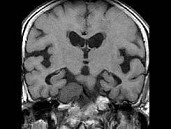

- 单项选择题男,46岁, 面部肌肉麻木、疼痛,咀嚼困难, 牙痛,MRI检查如图, 最可能的诊断是 ( )

B、三叉神经鞘瘤